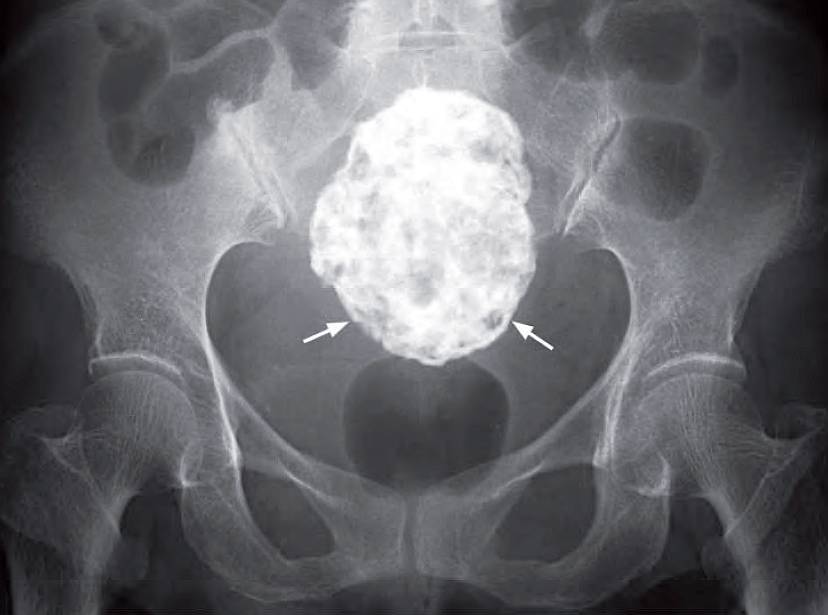

KUB Interpretation

A large amorphous, well-defined, ovoid, calcified mass in the pelvis – commonly seen in degenerated fibroids.